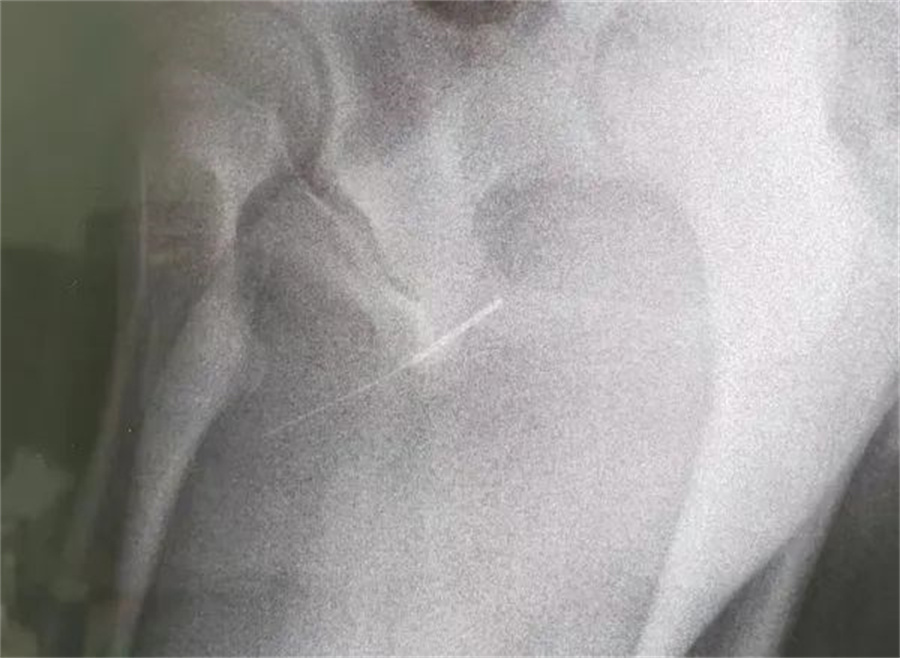

“孩子大概是中午的时候把银针塞进尿道中,因为针灸银针前段柔软纤细而末段又有增粗的螺旋状柄头,所以很难取出来。家长已经带他在当地医院拍片确诊,晚上7点多转到我们医院,当时孩子尿道口有血,疼痛难忍......”蜜桃视频

急诊外科接诊后立即收入院并第一时间做好手术准备,此时泌尿外科主任谢方达也紧急从家中赶到了医院,经过术前检查,确认银针卡在了接近球部尿道的部位,位置比较深,又没进入到膀胱里,如何尽快地取针成为一个颇具难度的挑战。

孩子家长和泌尿外科专家都希望用最微创的方式完成手术。但因孩子年龄小、尿道细,体重又偏大而难以实现,术中医生在保证对孩子造成伤害最小的前提下,采取隐匿小切口的方式,顺利将6.5cm的银针从尿道中刺破取出,为孩子解除了困扰,术后恢复三四天后即可顺利出院。